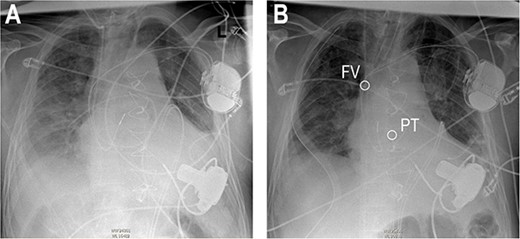

Re-sternotomy was performed. The pulmonary trunk (PT) was clamped. A 10-mm prosthetic polyester graft was anastomosed to the PT. After subxiphoid tunneling of the graft the transjugular outflow cannula was replaced by a cannula in the anastomosed graft. The cannula in the right FV remained in position in the right atrium (Figs 3 and 4). The hemodynamic situation with LVAD and RVAD flow improved immediately.

Surgical site after implantation of the cannula in the PT. AAo (ascending aorta), DL (driveline of left ventricular assist device), IVC (inferior caval vein), LAA (left atrial appendage), PT (pulmonary trunk), RPV (right pulmonary veins), RVAD (cannula of right ventricular assist device) SVC (superior caval vein).